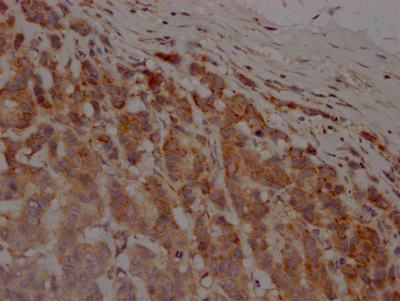

IHC image of CSB-RA595609A0HU diluted at 1:100 and staining in paraffin-embedded human breast cancer performed on a Leica BondTM system. After dewaxing and hydration, antigen retrieval was mediated by high pressure in a citrate buffer (pH 6.0). Section was blocked with 10% normal goat serum 30min at RT. Then primary antibody (1% BSA) was incubated at 4℃ overnight. The primary is detected by a Goat anti-rabbit IgG polymer labeled by HRP and visualized using 0.05% DAB.